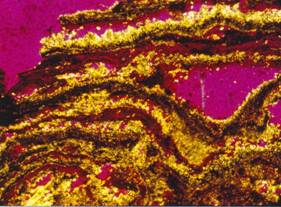

Střídající se vrstvy apatitu a

whewellitu s příměsí weddellitu.

Výbrus, polarizační mikroskop, zvětšeno 160x